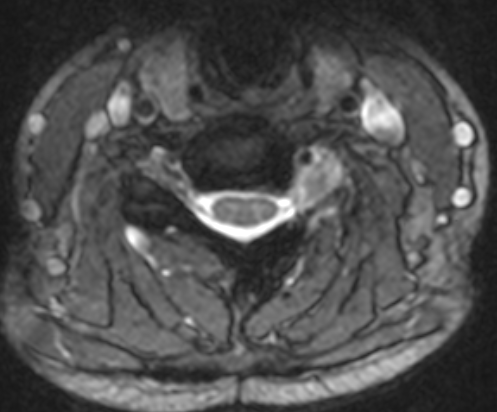

Imagen postoperatoria, sin clara captación nodular de gadolinio.